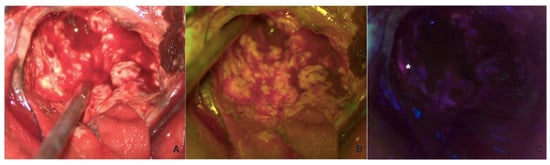

The surgical strategy involved a first white-light inspection of the tumor, and before excision, the fluorescent pattern was systematically analyzed with both fluorophores to highlight their differences (Figure 1). We can observe an overlap between the two fluorophores (B,C) despite 5-ALA being more prevalent, and structural alteration of the tumor parenchyma is visible even in white light (A).

Figure 1. Visualization in white light (A), FL 560 (B), and FL 400 (C) of the tumor before corticectomy.

Following the corticectomy, the first phase of debulking was performed using only fluorescein (with a shift to white light) to broadly delineate the tumor while easily controlling hemostasis. This phase was followed by a second look using 5-ALA with the possibility of switching between the two fluorophores and white light in cases of doubtful fluorescence, such as in the ependymal region (Figure 2).

Figure 2. Visualization in white light (A), FL 560 (B), and FL 400 (C) of the tumor during resection. In (C), a tumor residual visible on 5-ALA fluorescence, but not on SF or WL, is highlighted with the white asterisk.